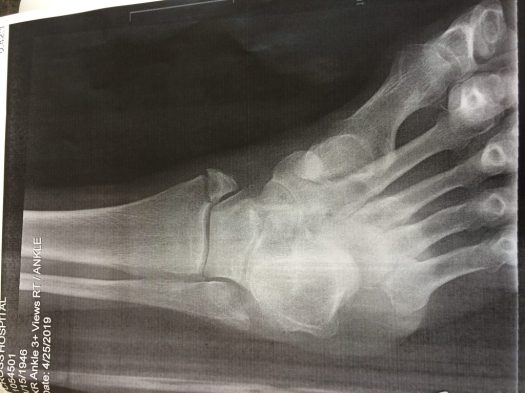

The broken part of my wife’s ankle is the traingle of bone floating near the tibia, to which it should be attached.

She’s had surgery and isn’t supposed to be walking on it for a month. But now, with the help of several screws holding parts together, she is on the mend.